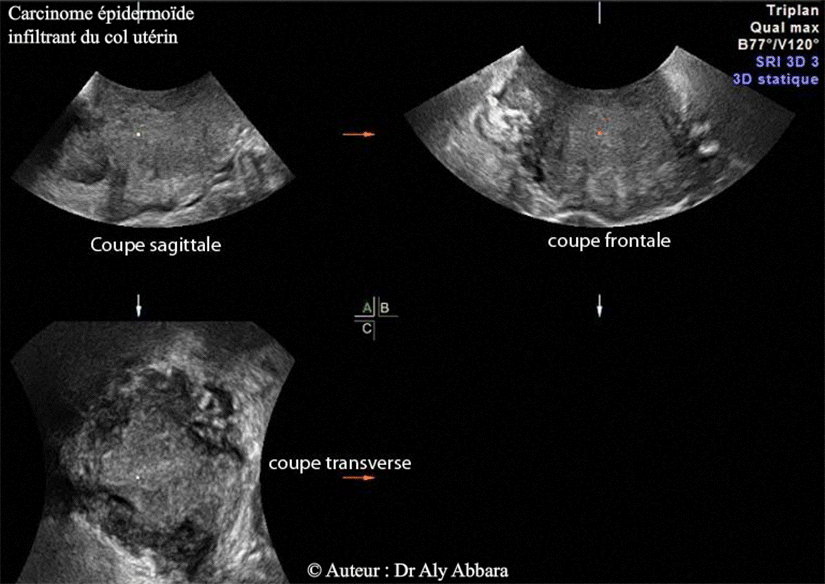

Coupe sagittale du col utérin et de la région isthmique de l'utérus

Carcinome épidermoïde infiltrant du col utérin

• L'aspect échographique d'un carcinome épidermoïde invasif, infiltrant du col utérin ; il s'agit d'un processus tumoral évoluant principalement au sein des structures internes du col.

• La coupe sagittale montre la présence :

• d'une hématométrie (estimée à 15 ml) ;

• d'un processus tumoral hétéroéchogène évoluant principalement au sein de la paroi postérieure du col utérin, puis partiellement dans sa paroi antérieure.

• Le mode D3 (Triplan) montre, sur la coupe transverse, l'extension du processus tumoral vers le paramètre droit, ce qui est en accord avec les données de l'examen gynécologique clinique qui montre la présence d'une ulcération limitée à la zone péri-orificielle externe du col utérin, avec augmentation du volume de la portion supravaginale du col, en particulier sa paroi postérieure, et enfin une infiltration des deux tiers internes du paramètre droit.

Carcinome épidermoïde du col de l'utérus - Images en 3D - triplan